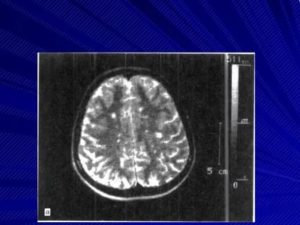

| Очаги демиелинизации на МРТ до и после лечения.Через 4 месяца от начала лечения видно уменьшение очагов – ремиелинизация(диагноз – рассеянный склероз, протекавший на фоне инфекции вирусомЭпштейн-Барр, микоплазмой и хламиией). Чем раньше начато лечение – темлучше прогноз на восстановление. |

Нередко пациентам назначается магнитно-резонансная томография, которая является популярной процедурой при подозрениях на патологии головного мозга. С её помощью можно понять, существуют ли патологические очаги, где они находятся, а также какое имеют количество.

Основной метод инструментальной диагностики – нейровизуализация. Очаги демиелинизации, расположенные в головном мозге, преимущественно выявляются при помощи исследования МРТ, на снимках отчетливо видны участки пораженной ткани диаметром не меньше 3 мм. Очаги демиелинизации в структурах ПНС обнаруживаются в ходе электромиографии. Ангиография показывает степень повреждения сосудов.

Диагностику заболевания осуществляют с помощью магнитно-резонансной томографии. При этом обнаруживаются множественные очаги демиелинизации. Преимущественно их обнаруживают в белом веществе головного мозга. Одновременно сосуществуют свежие и старые бляшки. Это является признаком постоянного процесса, объясняет прогрессирующий характер патологии.